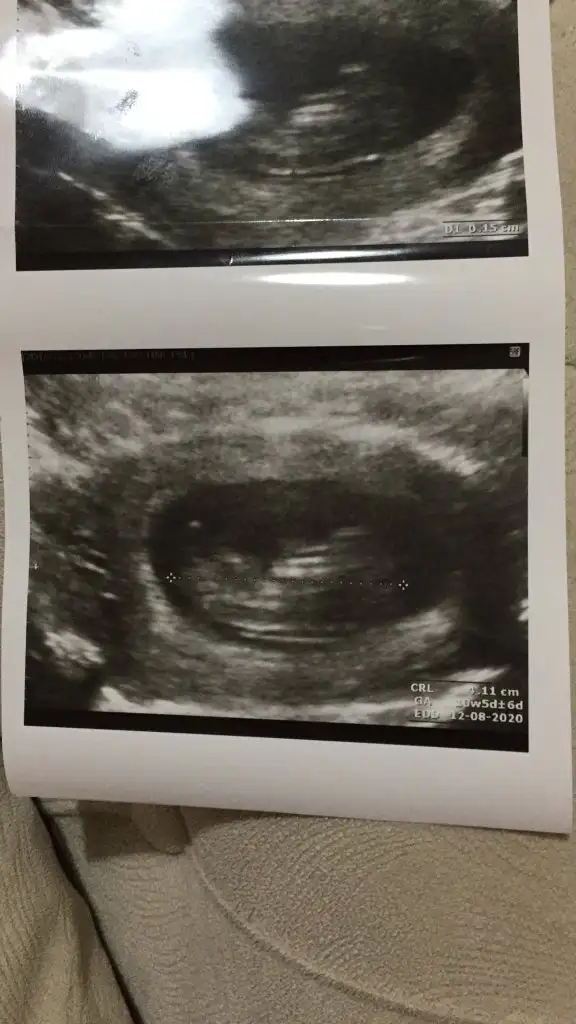

Haftam yaklaştıkça bir merak sardı.

O gözüken nub mu emin olamadım ama yine de bir atayım belki fikir yürüten olur didimm.

10+5 günlük bir kurbağa 🐸 🐣

Ne dersiniz?? Ikra meyra Ikra meyra

Net degil usg 11+ yada 12+ oldugunda paylaşın yada net varsa usg paylaşın